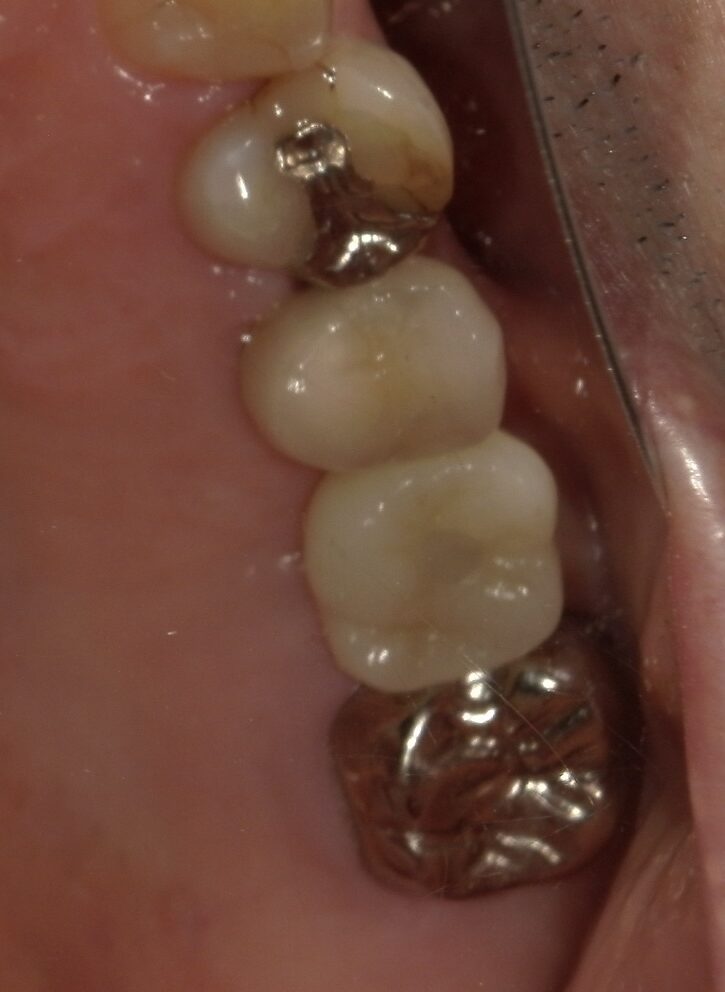

症状 『銀歯が痛くて噛めないので治して欲しい』との訴えで初めて来院 年齢・性別 40代女性 治療期間 約8ヶ月(抜歯する前〜インプラント治療完了まで) 治療方法 一度保存を試みたものの状態が悪く抜歯 その後インプラント治療を希望 費用 インプラント治療代 400,000円+税(手術、薬、被せ物などの費用全て含む) デメリット・注意点 歯が完全に割れていたこともあり骨の状態が非常に悪く、インプラント治療開始までに時間を要した 備考 銀歯が痛くて治して欲しいとのことで来院されました。 レントゲンの様子を見ても歯が割れている可能性は高かったですが、保存できる可能性もあるため一度銀のかぶせものを外して歯の状態を確認しました。 実際、根の状態を見てみるとかなり大きく穴があいていて保存は難しく抜歯することになりました。(下に写真あり) 抜歯後はインプラント治療をご希望されたため、骨を回復させたのちに治療を行いました。 歯の色は患者様のご希望で比較的白い歯の色を選択されました。 食事中も自分の歯のように噛めるとお喜びいただき、現在はメインテナンスに通っていただいており順調です。 -